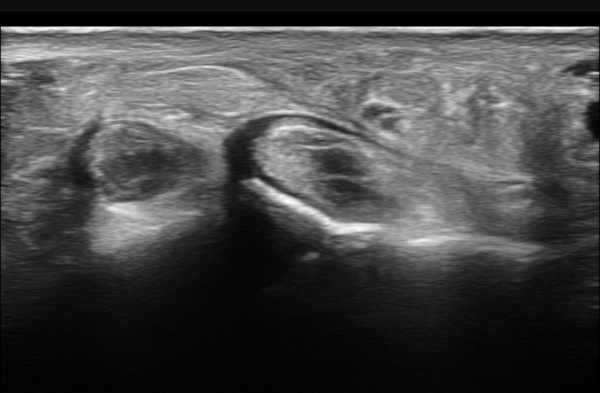

ÃÊÀ½ÆÄ ¼Ò°ß : ºñº¹½Å°æ Ⱦ´Ü¸é°Ë»ç¿¡¼­(»çÁø 1~13) ºñº¹½Å°æÀÇ Àú¿¡ÄÚ ºÎÁ¾°ú ´Üºñ°ñ°Ç³» ³¶Á¾¼º º´º¯ÀÌ °üÂûµÈ´Ù.